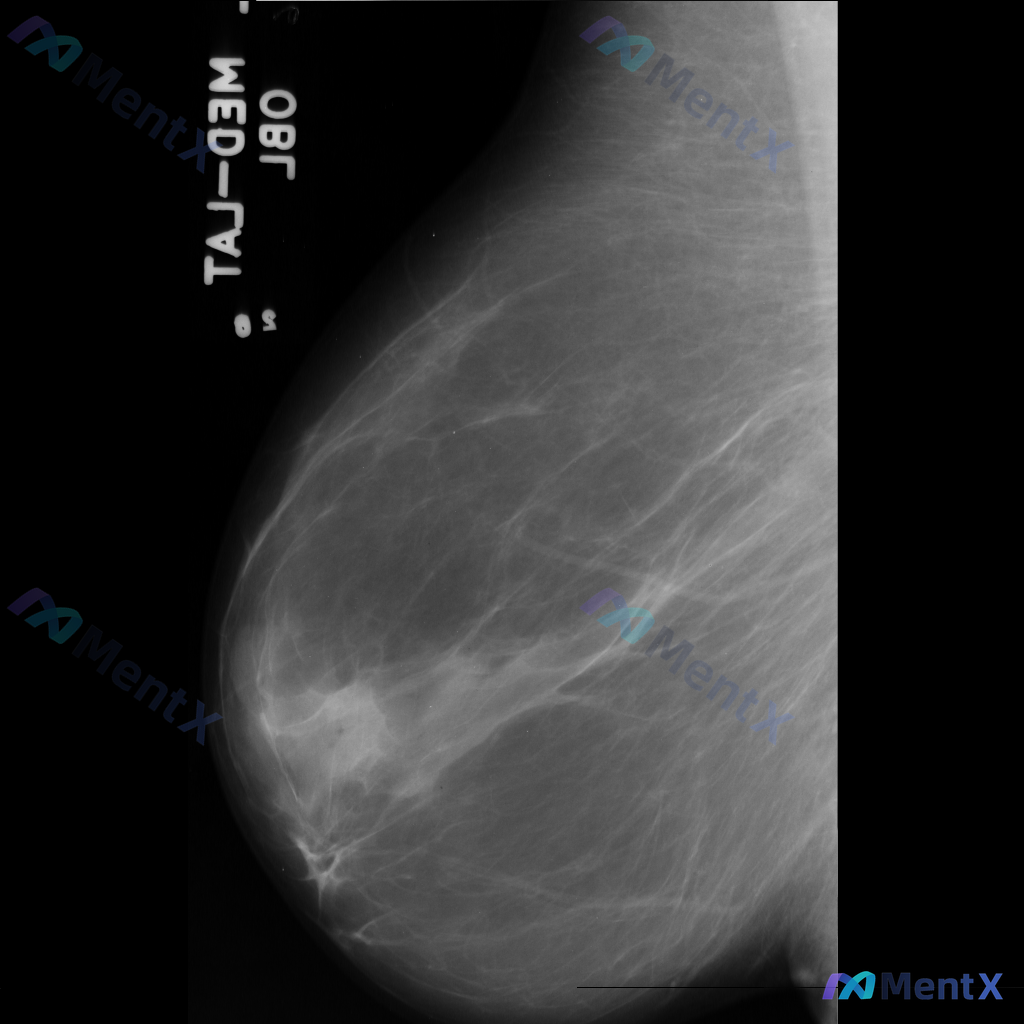

整理到一份乳腺钼靶影像资料,主要表现如下: - 乳腺中后部可见局灶性结构扭曲 - 无明确的肿块核心 - 周围腺体和脂肪界面被不规则牵拉 目前暂不提供既往影像对比和详细病史(手术史、外伤史、炎症史等)。 这种表现大家会先怎么判断?更倾向于往哪种方向考虑?